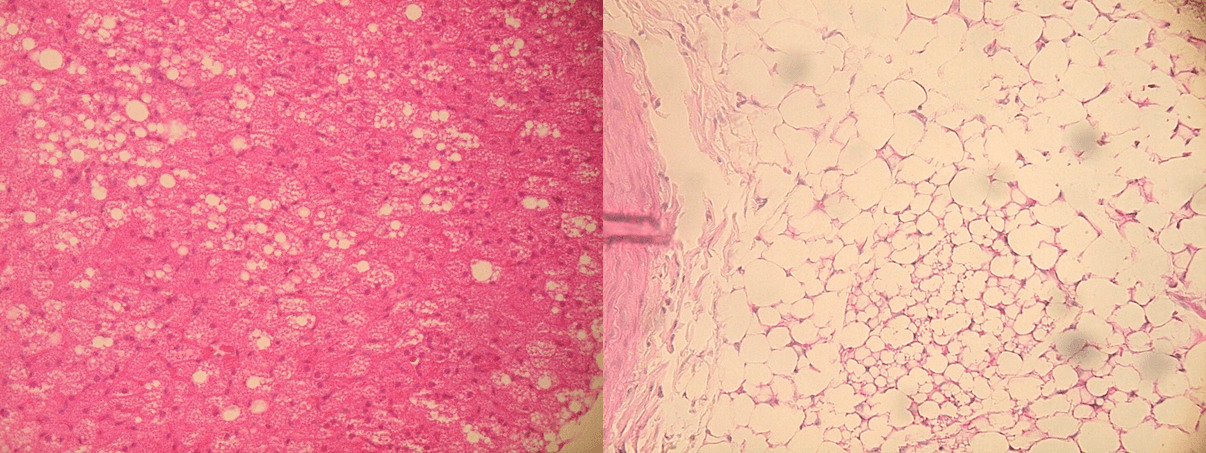

この原因を明らかにするために、腹部と胸部それぞれの血管周囲脂肪組織の詳細な解析を行ったところ、高脂肪食と高シュークロース食で影響を及ぼしやすい脂肪細胞の種類が異なることが示されました。高脂肪食は主に白色脂肪細胞に影響を与え、高シュークロース食は主に褐色脂肪細胞に影響を与えることが分かり、主に白色脂肪細胞で構成される腹部の血管周囲脂肪組織は、高脂肪食摂取の影響を受けやすく、褐色脂肪細胞が多く存在する胸部の血管周囲脂肪組織は、高シュークロース食摂取の影響を受けやすいことが示唆されました。

※2 白色脂肪細胞:見た目が白色に近いことから白色脂肪細胞と呼ばれる。中性脂肪を貯める機能を持つ細胞で、アディポサイトカインと呼ばれる生理活性物質を分泌する。アディポサイトカインは生命活動に重要な役割を持つ一方で、アディポサイトカインの分泌異常は、動脈硬化や糖尿病など様々な疾患に関与することが報告されている。お腹周りの脂肪は主に白色脂肪細胞で構成される。腹部の血管周囲脂肪組織を構成する脂肪細胞のほぼすべてが白色脂肪細胞である。

※3 褐色脂肪細胞:見た目が褐色に近いことから褐色脂肪細胞と呼ばれる。中性脂肪を燃焼して熱を作りだす細胞。胸部の血管周囲脂肪組織には褐色脂肪細胞が多く、白色脂肪細胞も一部存在する。